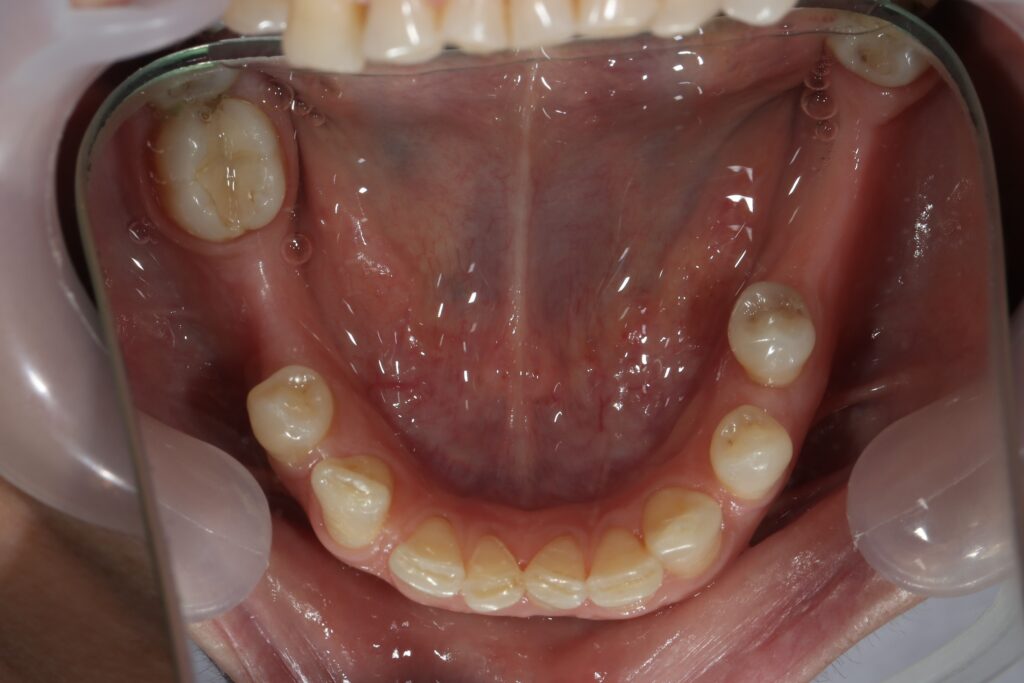

Ситуация до лечения